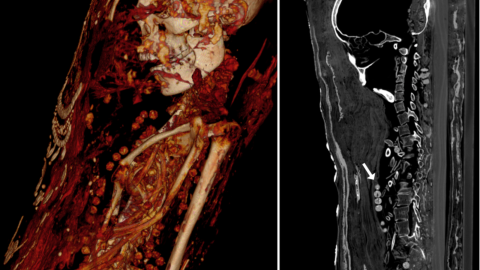

The decorated images showing who the mummies used to be. Credit: Zesch et al., PLOS One, 2020

The three mummies scanned are the only known examples of “stucco-shrouded portrait mummies.” As opposed to being buried in a coffin, these three were placed on wooden boards then wrapped in a textile and a shroud. They were then decorated with plaster, gold, and a whole-body portrait revealing what they looked like, how they styled their hair, and what they wore in life. All three were once buried in Saqqara, the great Necropolis just south of Giza.

They date back to the Late Roman Period in Egypt, and all three of them have had very exciting afterlives filled with stories about their discoveries and shifting ownership. Now, thanks to modern technology, we can learn about their lives.